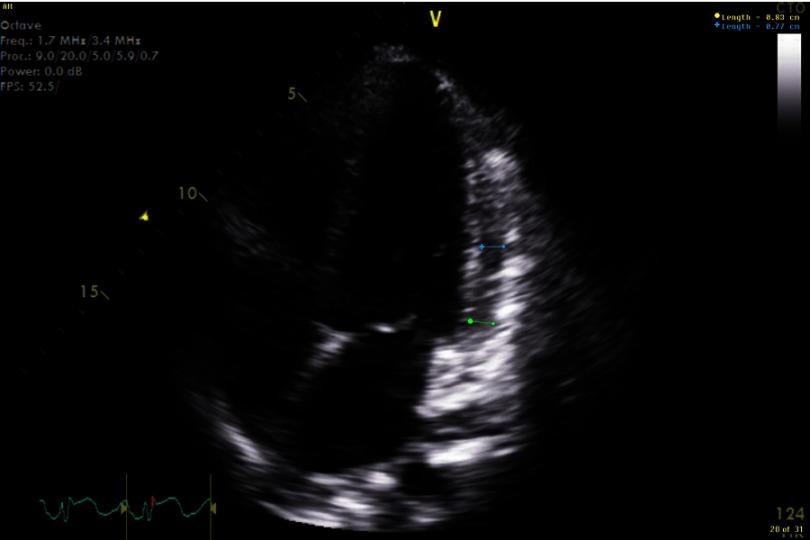

-associated myopericarditis (CAM) has been reported infrequently in the literature. We describe a case of immunocompetent young woman presenting with chest pain, with history of recent travel and diarrhea. Evaluation led to diagnosis of myopericarditis associated with this infection. The patient improved with conservative management. The pathogenesis of CAM remains unknown. Patients present with chest pain, heart failure, pulmonary edema and arrhythmias. Diagnostic evaluation includes EKG, cardiac enzymes, echocardiogram, cardiac MRI and stool culture. Conservative management recommended and routine use of antimicrobial therapy is controversial. CAM is a rare but severe complication of infection. It should be considered as a diagnosis in patients presenting with chest pain with associated gastrointestinal symptoms.